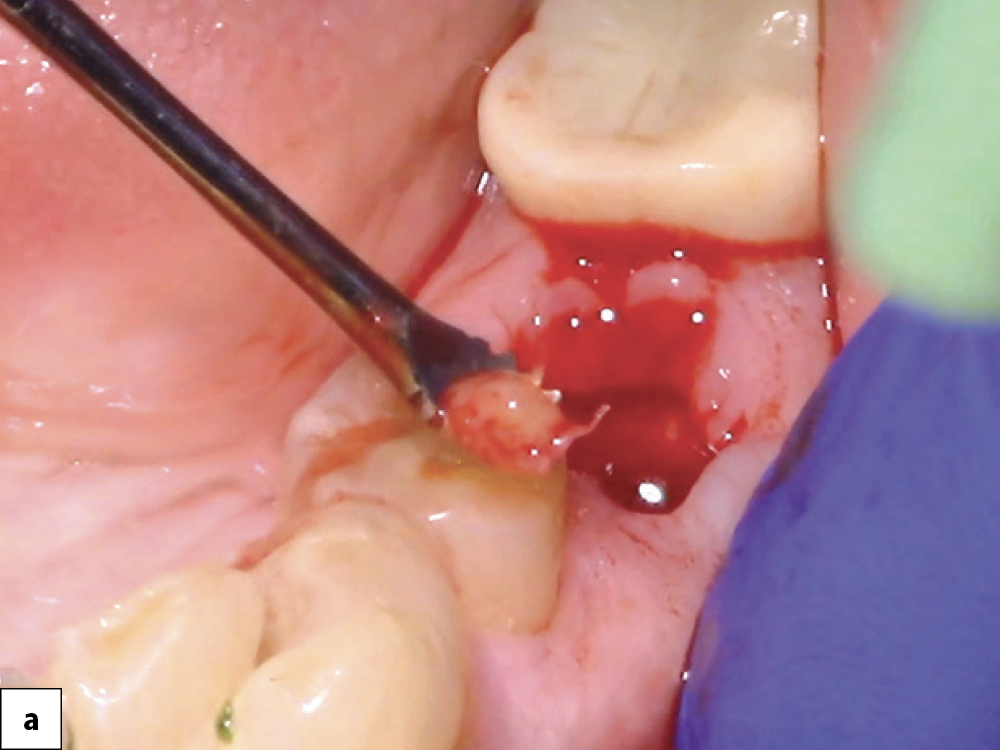

Socket Debridement A Tissue Removed

Socket Debridement B Sterilize Socket

Socket Debridement C Stimulate Bone Growth

Socket debridement: (a) Granulation tissue is completely removed from the socket using a serrated curette to facilitate successful bone healing and repair of the defect; (b) Irrigate socket with sterile saline; (c) To stimulate bone growth factors, the socket may be decorticated to initiate bleeding.